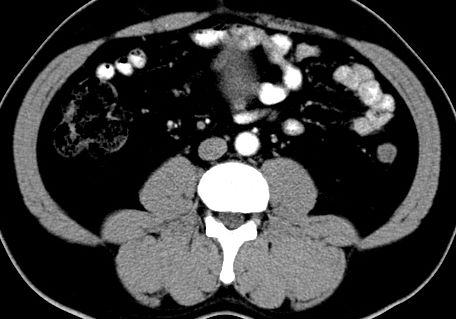

(腹腔)神经鞘瘤

男,48岁,间断性下腹不适1年。

手术探查

:距回盲部28厘米处肠系膜根部可见5*7cm左右包块,质中等硬度,活动度尚可,肝、胆、胰、脾肾未见明显异常。

病理

:(腹腔)

神经鞘瘤

,伴出血、坏死及囊性变,伴淋巴结反应性增生。

免疫组化结果

:sma(-), desmin(-), cd117(-), s-100(+++), nf(-),vimentin(+++).